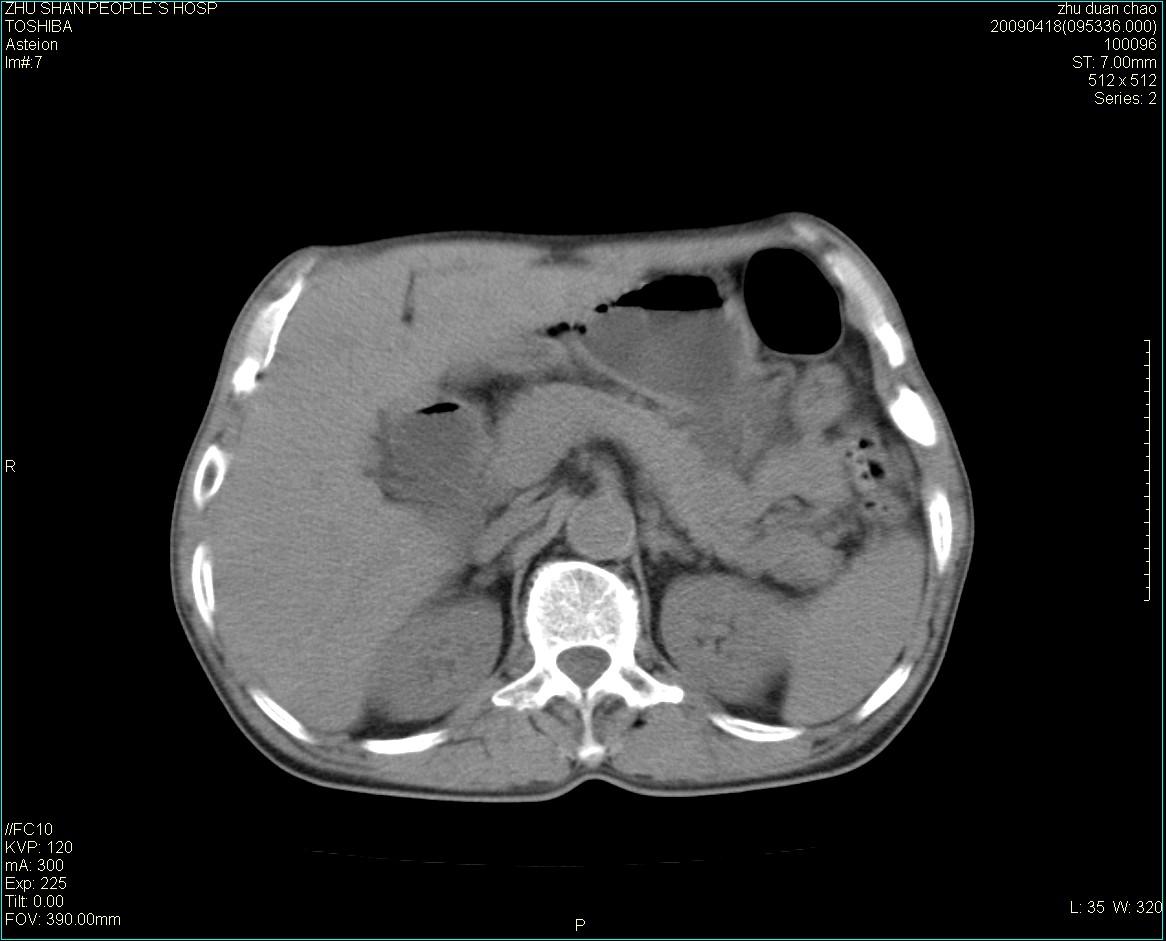

以下是引用余辉在2009-4-22 10:48:00的发言:[br]结肠肝曲附近肠段包块,病灶密度不均匀,周围肠系膜脂肪混浊,见多枚淋巴结肿大,考虑结肠癌可能性大,病灶累及范围较广建议进一步检查除外其他

以下是引用随光逐影在2009-4-22 11:57:00的发言:[br]考虑肠道肿瘤(间质瘤?)可能性大。

以下是引用ydx_74在2009-4-22 14:39:00的发言:[br]结肠癌周围侵犯可能,不能完全除外炎性病变